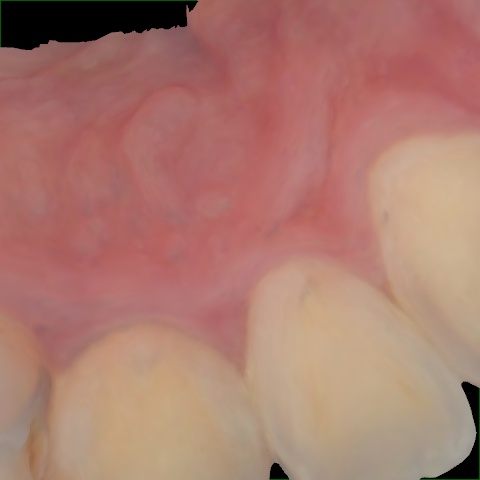

Annotated as "Good"